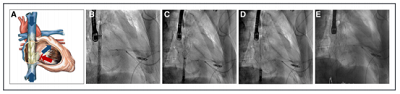

SapienXT(愛德華)

Sapien XT 是由美國愛德華公司研發(fā)的一款經(jīng)導(dǎo)管主動(dòng)脈瓣置換系統(tǒng)。該產(chǎn)品早期救治性應(yīng)用于重度 TR 時(shí)展示了較高的操作成功率[77]。然而,隨后的 TRICAVAL 隨機(jī)對(duì)照試驗(yàn)卻因?yàn)榘昴にㄈ矢撸?8.5%)且臨床癥狀和運(yùn)動(dòng)能力無顯著改善而提前終止,研究結(jié)果顯示其并不優(yōu)于藥物治療[78]。評(píng)估下腔靜脈植入 Sapien XT 安全性與有效性的 HOVER 研究僅納入 6 例患者后即處于停止招募狀態(tài)[79]。雖然經(jīng)皮腔靜脈內(nèi)植入瓣膜有效改善呼吸困難,但由于患者已發(fā)展為重度 TR,右心嚴(yán)重?cái)U(kuò)張,已經(jīng)缺乏逆重塑的潛能,對(duì)于早期瓣膜性心衰病例,缺乏有效的臨床數(shù)據(jù)[76]。

▲ Sapien XT 三尖瓣異位置換系統(tǒng)植入示意 (資料來源:Percutaneous transfemoral management of severe secondary tricuspidregurgitation with Edwards Sapien XT bioprosthesis: first-in-man experience. J Am Coll Cardiol. 2013 May 7,蛋殼研究院)